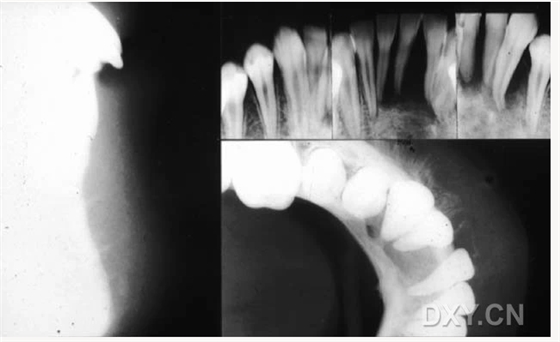

涎石病

骨髓炎